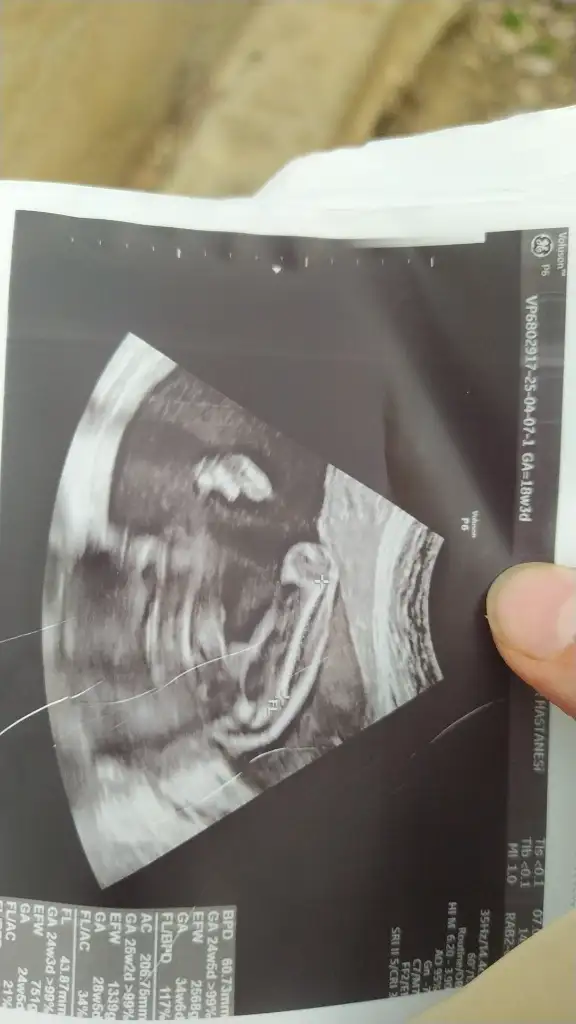

Kızlar 12 haftalık gebeyim. Nub teorisine göre cinsiyet tahmini yapabilir misiniz? İlk bebeğimiz ve biz cinsiyeti çok merak ediyoruz